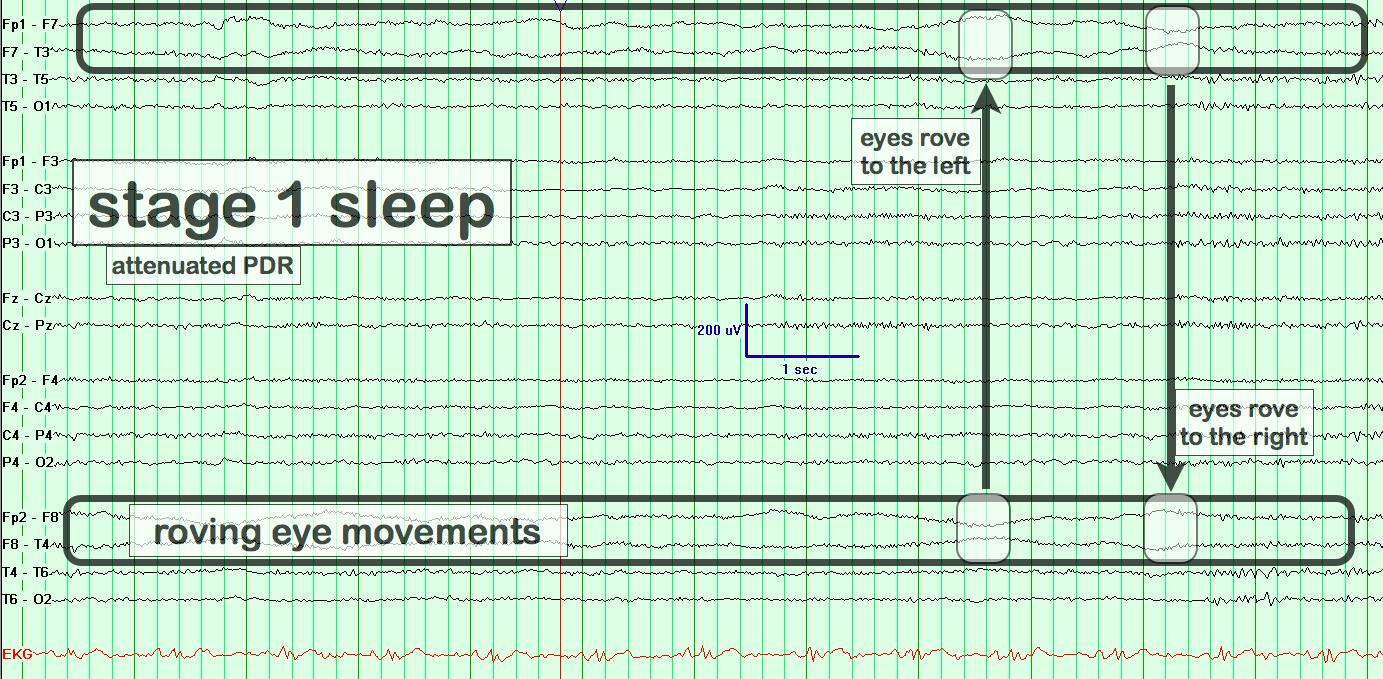

Roving Eye Movements

eegatlas-online.com

eegatlas-online.com

artifacts eye roving movements eegatlas online

Roving Eye Movements

eegatlas-online.com

eegatlas-online.com

eye roving movements artifacts eegatlas online